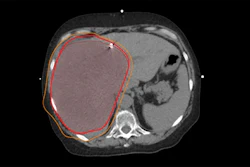

Dr. Adriano Dias highlighted results of a trial using Pylarify radiotracer in selecting patients for focal ablative therapy. Image courtesy of Adriano Dias.

Dr. Adriano Dias highlighted results of a trial using Pylarify radiotracer in selecting patients for focal ablative therapy. Image courtesy of Adriano Dias.Forty out of 67 (60%) lesions identified in patients on PET, mpMRI, or PET/MRI were malignant, and 34 of these 40 (85%) were clinically significant, according to the findings. On a lesion-level analysis in these, the sensitivity of PET was higher than of mpMRI and PET/MRI (91% vs. 76% and 79%), but it showed a lower specificity (39% vs. 85% and 88%, p < 0.001). The calculated AUCs were 0.65 for PET, 0.81 mpMRI, and 0.84 for PET/MRI.